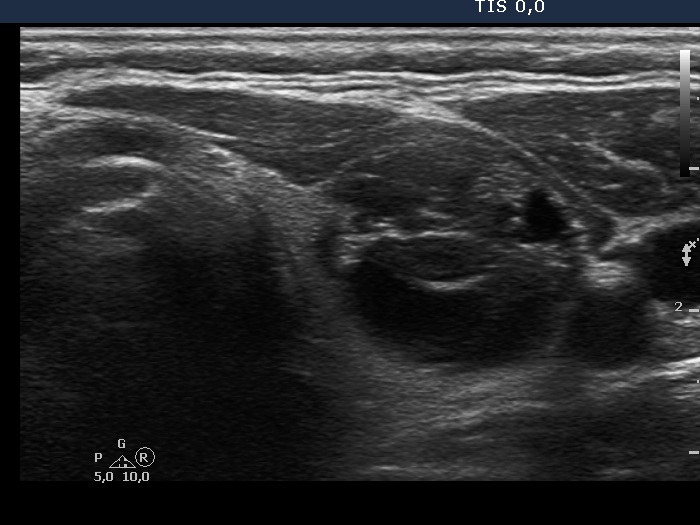

Left lobe, transverse scan. This lobe has a large cystic nodule.